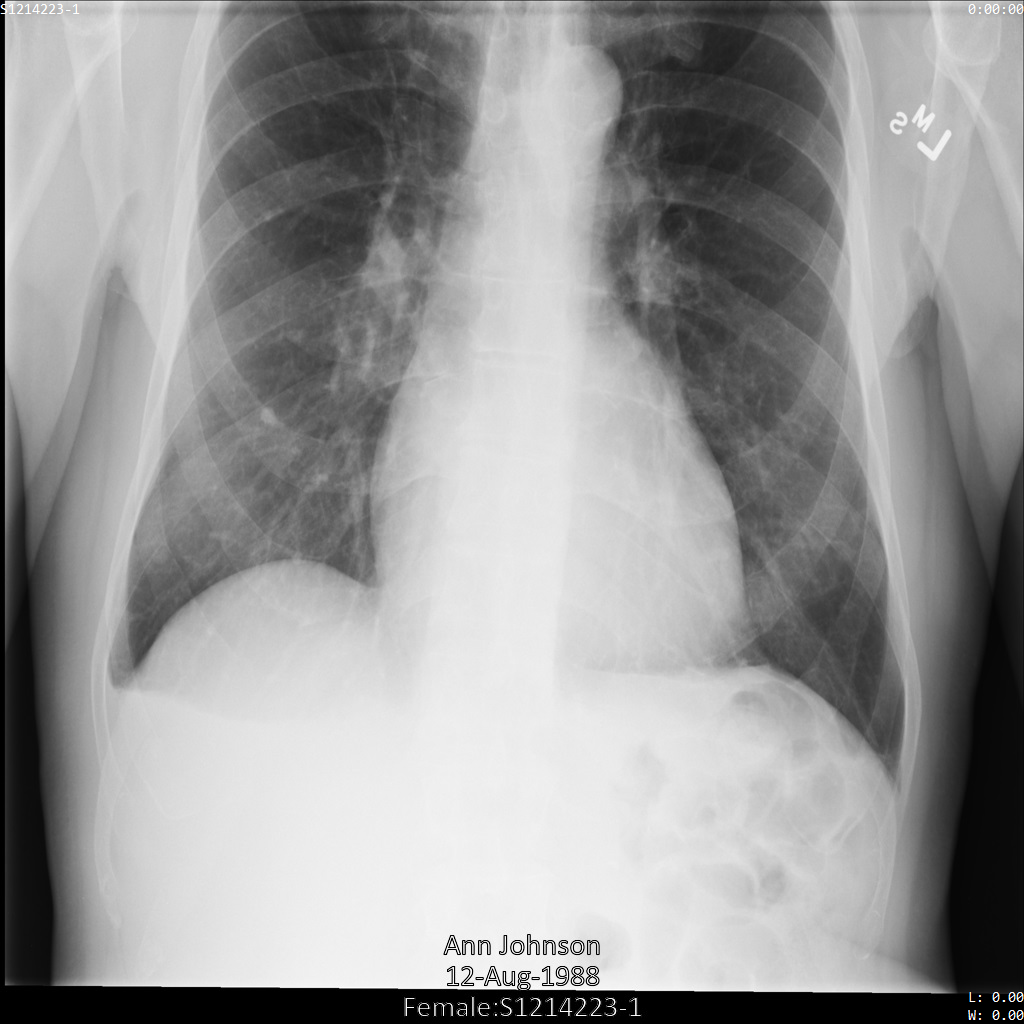

Chacune des sections suivantes fournit des exemples d'anonymisation de données DICOM à l'aide de différentes méthodes. Une sortie de l'image anonymisée est fournie avec chaque échantillon. Chaque exemple utilise l'image d'origine suivante comme entrée :

Vous pouvez comparer l'image de sortie de chaque opération d'anonymisation à cette image d'origine pour voir les effets de l'opération.

Une fois l'image envoyée à l'API Cloud Healthcare, elle apparaît comme suit. À l'exception des balises fournies dans la liste de suppression, seul PatientBirthDate est supprimé dans l'image, car il s'agit de la seule balise de la liste de suppressions qui correspond aux métadonnées visibles dans l'image.

Bien que le PatientBirthDate dans l'angle supérieur de l'image ait été masqué conformément à la configuration de la liste removelist, les données de santé protégées incrustées en bas de l'image sont conservées. Pour supprimer également le texte incrusté, consultez la section Masquer le texte incrusté dans les images.